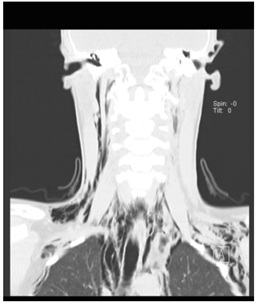

From the additional study, blood tests had no elevation of inflammatory parameters. Chest radiography showed cervical subcutaneous emphysema, suggesting the possibility of Pneumomediastinum (Figure 1).

Figure 1: Chest radiography revealing cervical subcutaneous emphysema. Pneumomediastinum may be seen, extending into the neck and outlining the pericardium.